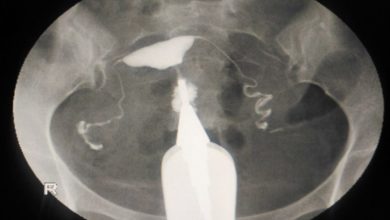

Balonlu HSG kateteriyle ağrısız rahim filmi nasıl çekilir?

Rahim filmi çekilmesi sırasında rahim boşluğu ve tüpler rahim ağzından verilen 5-10 ml (1-2 çorba kaşığı) ilaçla doldurulur. Eskiden ilacı…

Rahim boşluğu içinde mevcut olabilecek yapışıklık, polip gibi patolojiler ile rahmin doğumsal anomalilerinin rahim filminde görülebilmesi, teşhis edilebilmesi için filmlerin…